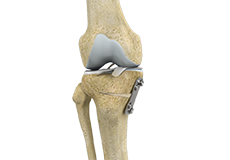

Patellofemoral Knee Replacement

The knee can be divided into three compartments: patellofemoral, the compartment in front of the knee between the kneecap and thighbone, the medial compartment, on the inside portion of the knee, and lateral compartment which is the area on the outside portion of the knee joint.

Am I a Candidate for Knee Surgery?

Arthritis of the knee can cause pain and stiffness, making regular activities such as walking and bending difficult. As arthritis progresses, conservative treatments tend to lose their efficacy and more definitive treatment should be considered. Knee replacement surgery involves replacing worn or damaged joints with implants to reduce pain and improve movement.